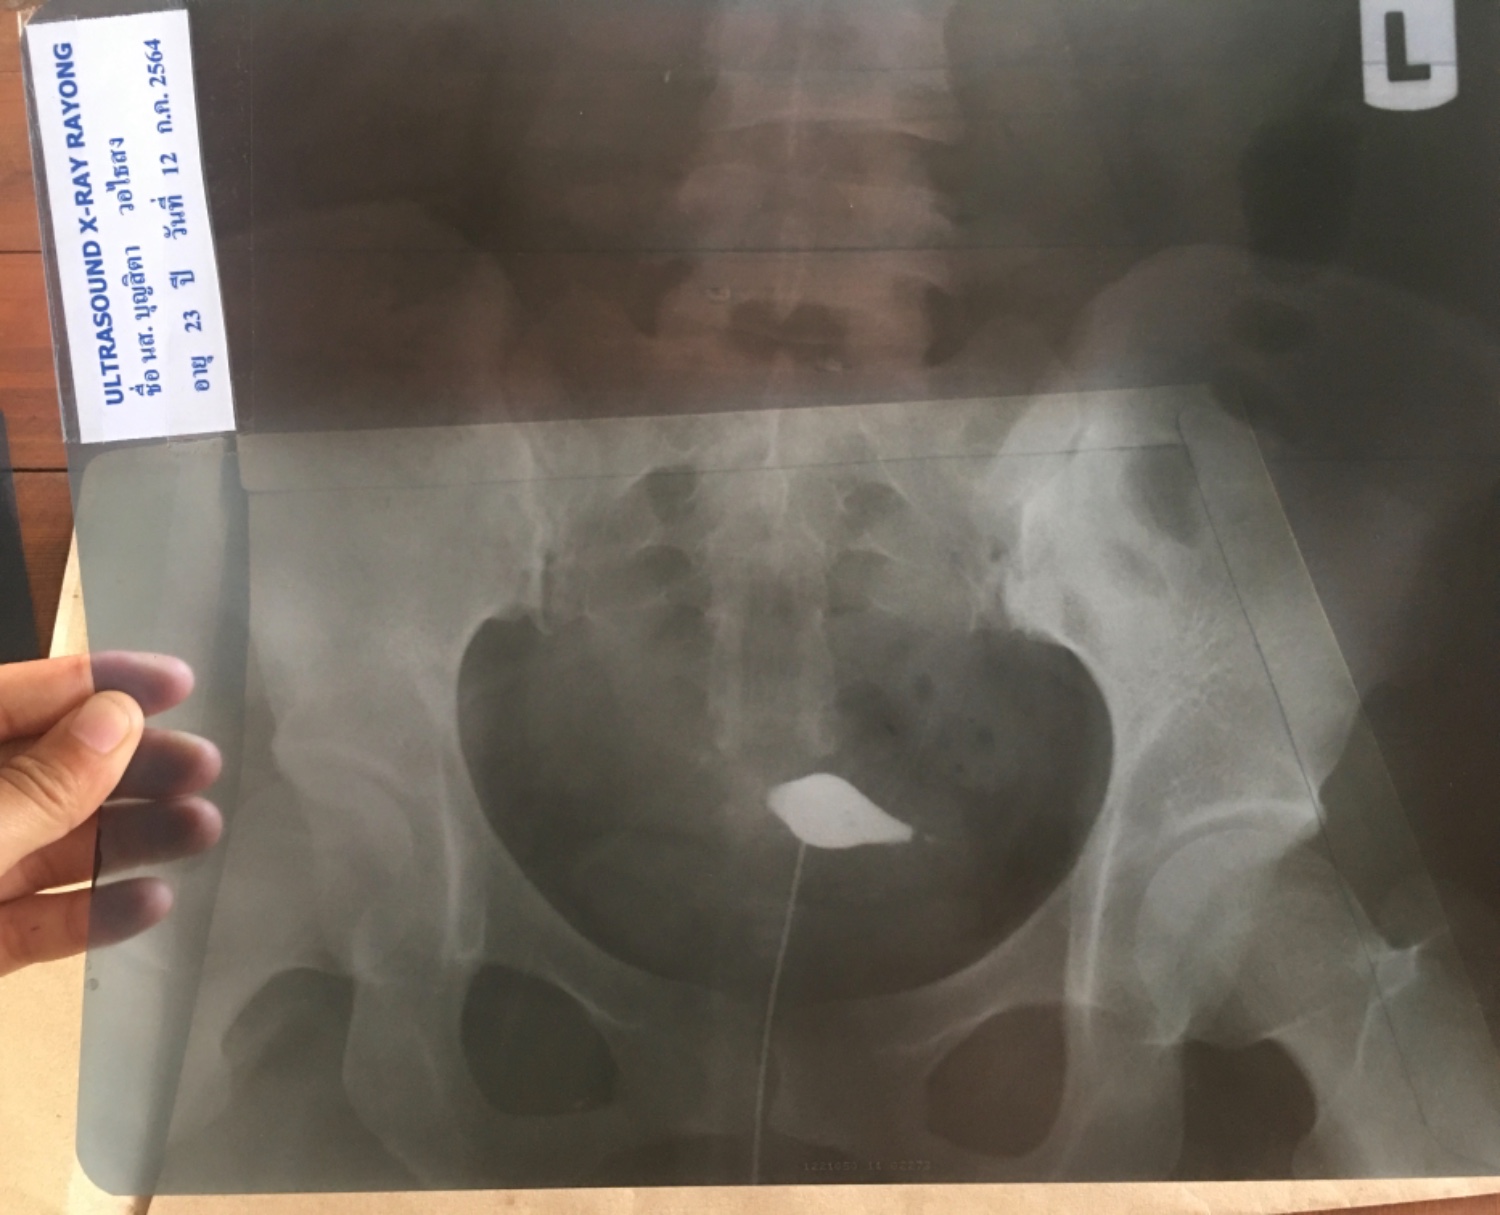

ช่วยดูหน่อยคะ พอดีไปฉีดสีดูท่อนำไข่มา หมอไม่ได้บอกอะไรเลยคะ ผลแบบนี้คืออะไร ตันหรือป่าว หรือ ปกติ

พอดีเพิ่งไปฉีดสีดูท่อนำไข่มา* ตอนตรวจเห็นคุณหมอที่ทำการตรวจให้ไม่ได้บอกผล แต่ให้ผลเอ็กสเรย์กลับมา (พอเอาพจนานุกรมแปลผลได้) และได้บอกแค่ว่าเสร็จแล้วจะมีเลือดจะออ